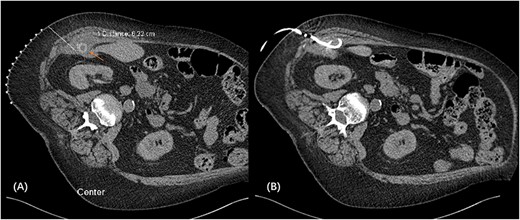

We proceeded with a multiphase computed tomography (CT) scan which was suggestive of a mixed density lesion measuring 62 × 86 × 98 mm arising from the right posterior transverse abdominis/internal oblique muscle, with a well-defined rounded calcific focus at its inferior aspect likely representing a dropped gallstone (GS) associated with abscess formation (Fig. 1). She was commenced on intravenous antibiotics and, in review of her medical comorbidities and DAPT on board, underwent image-guided percutaneous drainage of the gallstone associated abscess collection in the first instance. Following a course of intravenous and oral antibiotics, she was followed up in the outpatient clinic where the drain was removed after 9 days as the output was serous and minimal. Clearance from anaesthetics and cardiology were obtained during pre-operative evaluation of fitness towards surgery, including an ECHO which demonstrated severe left atrial enlargement and moderate mitral stenosis but normal systolic function. DAPT was withhold since initial admission. She underwent an elective procedure 4 weeks later from the initial presentation with pre-operative CT-guided drain localization of the gallstone (Fig. 2) followed by an extra-peritoneal approach of exploration of the right flank. A single 18 × 15 × 14 mm intramuscular gallstone was removed from a deep intramuscular abscess cavity at 6 cm, with fibrous and inflamed tissue surrounding the stone (Fig. 3). Histopathology demonstrated a gallstone with acute inflammation and acellular debris. The postoperative course was uncomplicated with patient discharged on Day 3 post operation and remained well at outpatient follow-up with DAPT restarted.

CT scan demonstrating retained gallstone with associated abscess ~62 × 86 × 98 mm in the right flank involving the right posterior transverse abdominis/internal oblique muscle in the coronal (A) and axial (B) views.